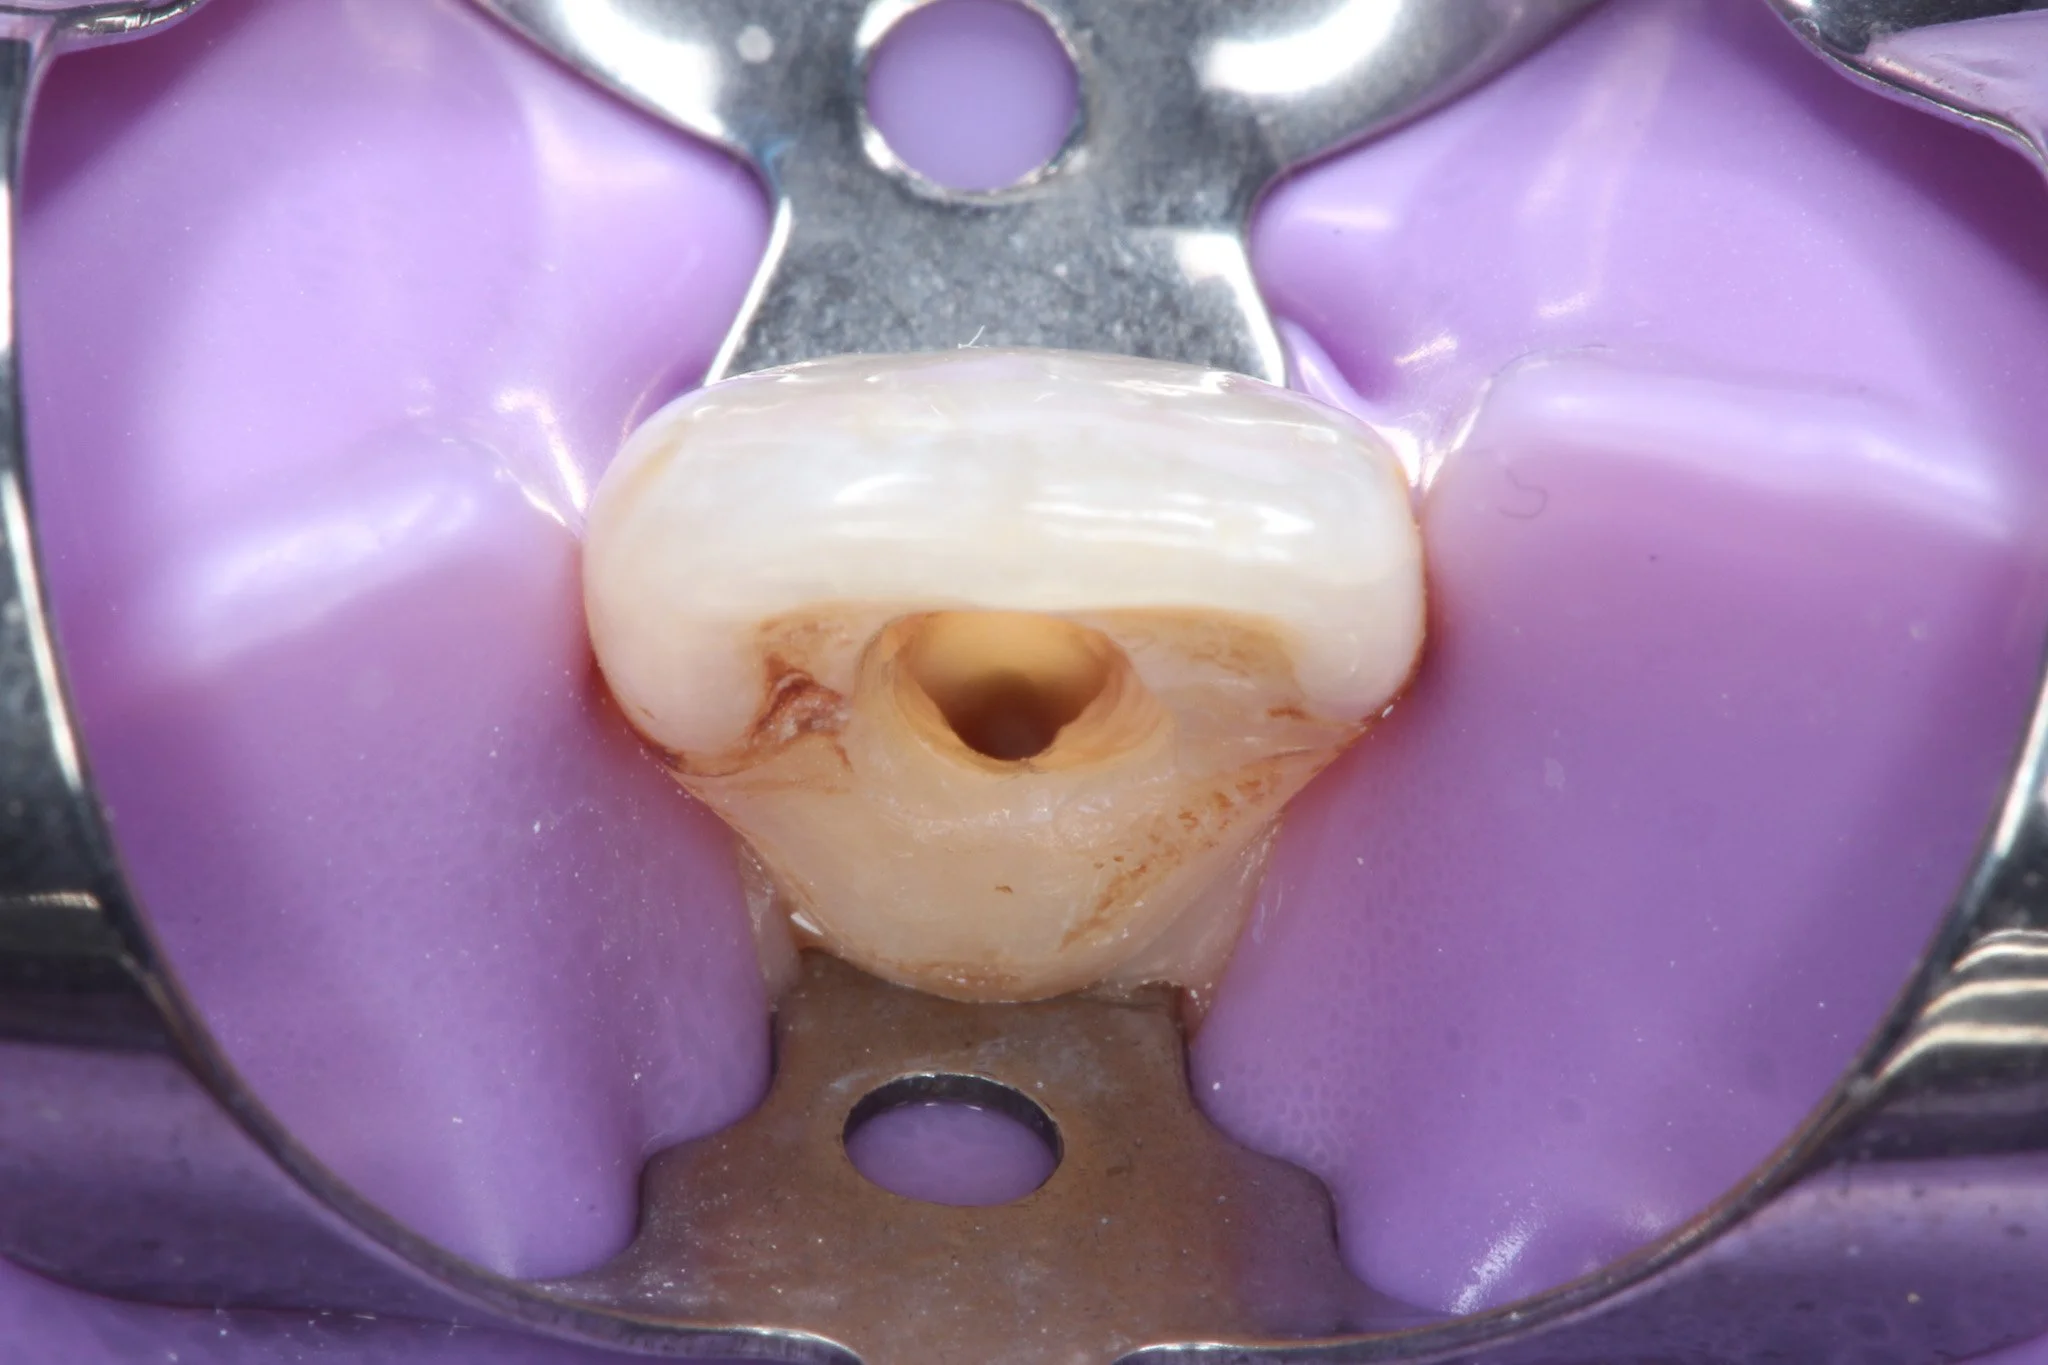

Close-up of a dental crown being prepared, with a purple rubber dam in place.

A small hole in the back on an incsor tooth to gain access to the nerve

Accessing the Nerve of the Tooth

Your dentist will drill a small opening in the top of the tooth (back teeth) or the back of the tooth (front teeth) to reach the pulp chamber inside. This exposes the infected nerve tissue.